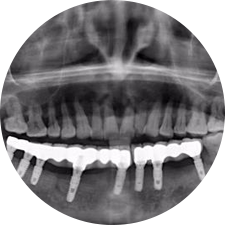

口腔種植是將人工牙根通過手術(shù)植入牙骨內(nèi),獲得牙槽骨牢固的支持,通過特殊的裝置和方式連接牙修復(fù)體,獲得與天然牙功能、結(jié)構(gòu)以及美觀相似的效果。

河北惟德口腔醫(yī)院擁有國內(nèi)豐富的半口/全口、即刻負(fù)重種植案例,十八年案例跟蹤分析,總結(jié)梳理出的各種不同類型的種植案例,Nobel種植體系針對半口/全口缺牙患者,通過4-8顆種植體可快速達(dá)到牙齒重建,不僅植入種植體較少,節(jié)省費(fèi)用,手術(shù)時間更短。

術(shù)前患者CBCT口掃1:1三維重建,模擬手術(shù)過程及預(yù)測術(shù)后治療效果,確定每顆植體植入的適合的種植位點(diǎn)、深度及角度,有效避免損傷頜骨重要解剖結(jié)構(gòu),提高手術(shù)準(zhǔn)確度與安全性。

Noble口腔種植體系基本不受年齡限制,適用于缺牙修復(fù),也適用于牙槽骨萎縮、骨質(zhì)疏松、高血壓、糖尿病、超高齡的患者,即種即用,只需少量微小種植體,便可輕松微痛快速重建全口咬合,特殊力學(xué)設(shè)計(jì),針對許多年紀(jì)較大,骨質(zhì)條件差,身體耐受力差的缺牙老人也能完成“即種即用”,受到廣泛好評。

惟德口腔種植體系是以患者感受為中心,取代傳統(tǒng)種植牙手術(shù)需要翻瓣、打孔、縫合,術(shù)前、術(shù)中、術(shù)后的繁復(fù)流程,采用3D導(dǎo)航微創(chuàng)準(zhǔn)確種植技術(shù),通過數(shù)字化CAD/CAM掃描技術(shù)獲得缺牙患者口腔數(shù)據(jù),以數(shù)據(jù)為基礎(chǔ)重建口腔模型進(jìn)行模擬種植。

術(shù)前將患者口內(nèi)的CBCT數(shù)據(jù)及咬合關(guān)系上傳到計(jì)算機(jī)中,建立1:1三維重建,模擬手術(shù)過程及預(yù)測術(shù)后治療效果,找出較佳種植位點(diǎn)、深度及角度,獲取實(shí)際種植體在頜骨內(nèi)的具體三維位置,有效避免損傷頜骨重要解剖結(jié)構(gòu),大大降低手術(shù)風(fēng)險,提升種植成功率。